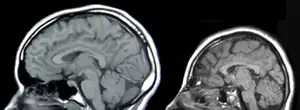

| Neural scans of a person without micropcephaly (left) and a patient with microcephaly. | |